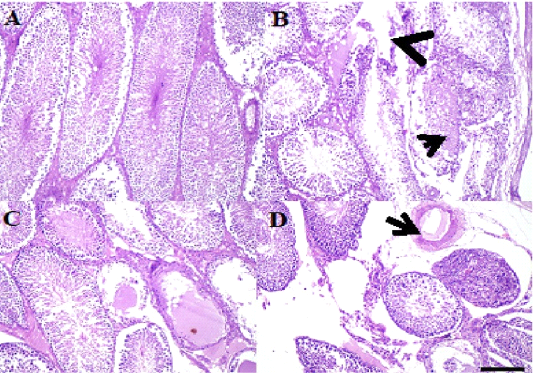

A: Photo micro graph of male rat seminal vesicle (control) showing normal tubuloalveolar glands and secretion, glandular structure, Trabeculae and covering tunica were normal (H&E; x100) . B: Photo micro graph of male rat Seminal vesicle showing normal tubule alveolar glands and edema in the smooth muscles, all the glandular structure appeared normal while tunica muscularis were edematous arrows (H&E; x100). C: Photo micro graph of male rat seminal vesicle showing partial desquamation of some glandular epithelium (arrows) and foamy secretion, some glands had partially desquamated epithelium and filled with foamy esinophilic colloidal secretion (H&E; x100). D: Photo micro graph of male rat seminal vesicle showing hyperplastic glands without secretion (arrows), tubuloalveolar glands were either hype plastic without secretion. Tunica muscularis had partial edema or necrosis (H&E; x100).